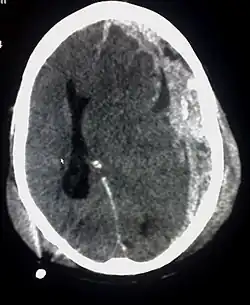

Niet-aangeboren hersenletsel (NAH) is een verzamelnaam voor alle letsels aan de hersenen die ontstaan zijn na de geboorte. Vaak heeft een persoon dan al een goede, normale ontwikkeling laten zien en ontstaat er vrij plotseling een afwijking door verschillende oorzaken, waardoor een of meerdere functies van de hersenen wegvallen of slechter worden.

De oorzaken van niet-aangeboren hersenletsel zijn zeer gevarieerd en omvatten onder andere:

- stoornis in de bloedtoevoer naar de hersenen (bijvoorbeeld bij trombose, een hersenbloeding, cerebrovasculair accident (CVA) of hartstilstand)

Traumatische oorzaken

- een (verkeers)ongeluk met als gevolg hersenletsel

- een val op het hoofd

- een klap op het hoofd met een zwaar voorwerp

- een schietpartij (kogel in het hoofd)